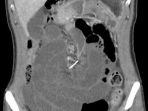

Kram Perut Berbulan-bulan, Perempuan Ini Kemasukan Kawat Gigi di Ususnya

Perempuan 30 tahun di Perth, Australia, itu awalnya sempat memeriksa ke rumah sakit atas keluhan kram pada perutnya.